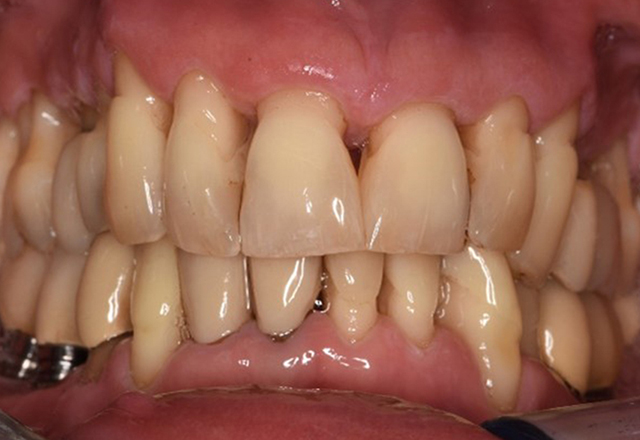

Die gesunde Patientin mit parodontaler Vorerkrankung

Die 68-jährige Patientin hat keine zahnmedizinisch relevanten allgemeingesundheitlichen Vorerkrankungen oder Medikation, auch aus dem Lebensstil ergibt sich kein besonderes Risiko. Die Patientin hat zwei Implantate (3. Quadrant, seit fünf Jahren) sowie eine parodontale Vorerkrankung (Parodontitis Stadium IV, Grad B) mit Zahnverlust. Derzeit zeigen sich stabile parodontale Verhältnisse. Für die Prophylaxesitzung ergeben sich vier Empfehlungen in den Bereichen Anamnese/Befund, Motivation/Instruktion, der Wahl der geeigneten Instrumente und für Resümee/Folgetermin. mehr Infos

NIWOP – No Implantology without Periodontology